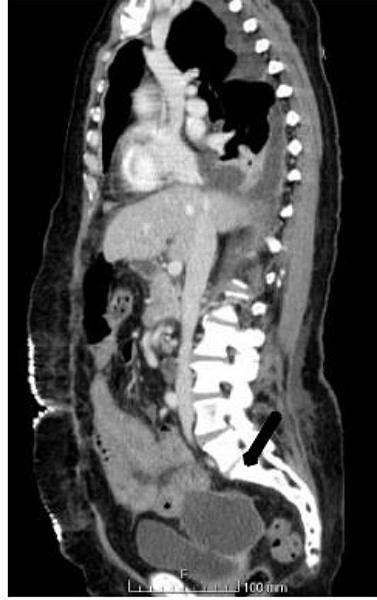

An abdominal computed tomography (CT) scan was performed, which identified an internal hernia at the root of the right mesentery, an apparent abscess in the right lung base (65 × 55 mm) (Fig. 1) as well as elevation of the right diaphragmatic hemi-dome with Chilaiditi sign (Fig. 2).

The patient underwent exploratory laparotomy, and there was a right diaphragmatic hernia with an intestinal loop in the chest. The hernia orifice was enlarged and the jejunal loop was reduced, which was necrotic without perforation (Fig. 3). Segmental enterectomy with later-lateral anastomosis was performed and a diaphragmatic repair was done with non-resorbable suture thread (Fig. 4). The abdominal and the right pleural cavities were washed and a chest tube was placed in the fifth intercostal space.